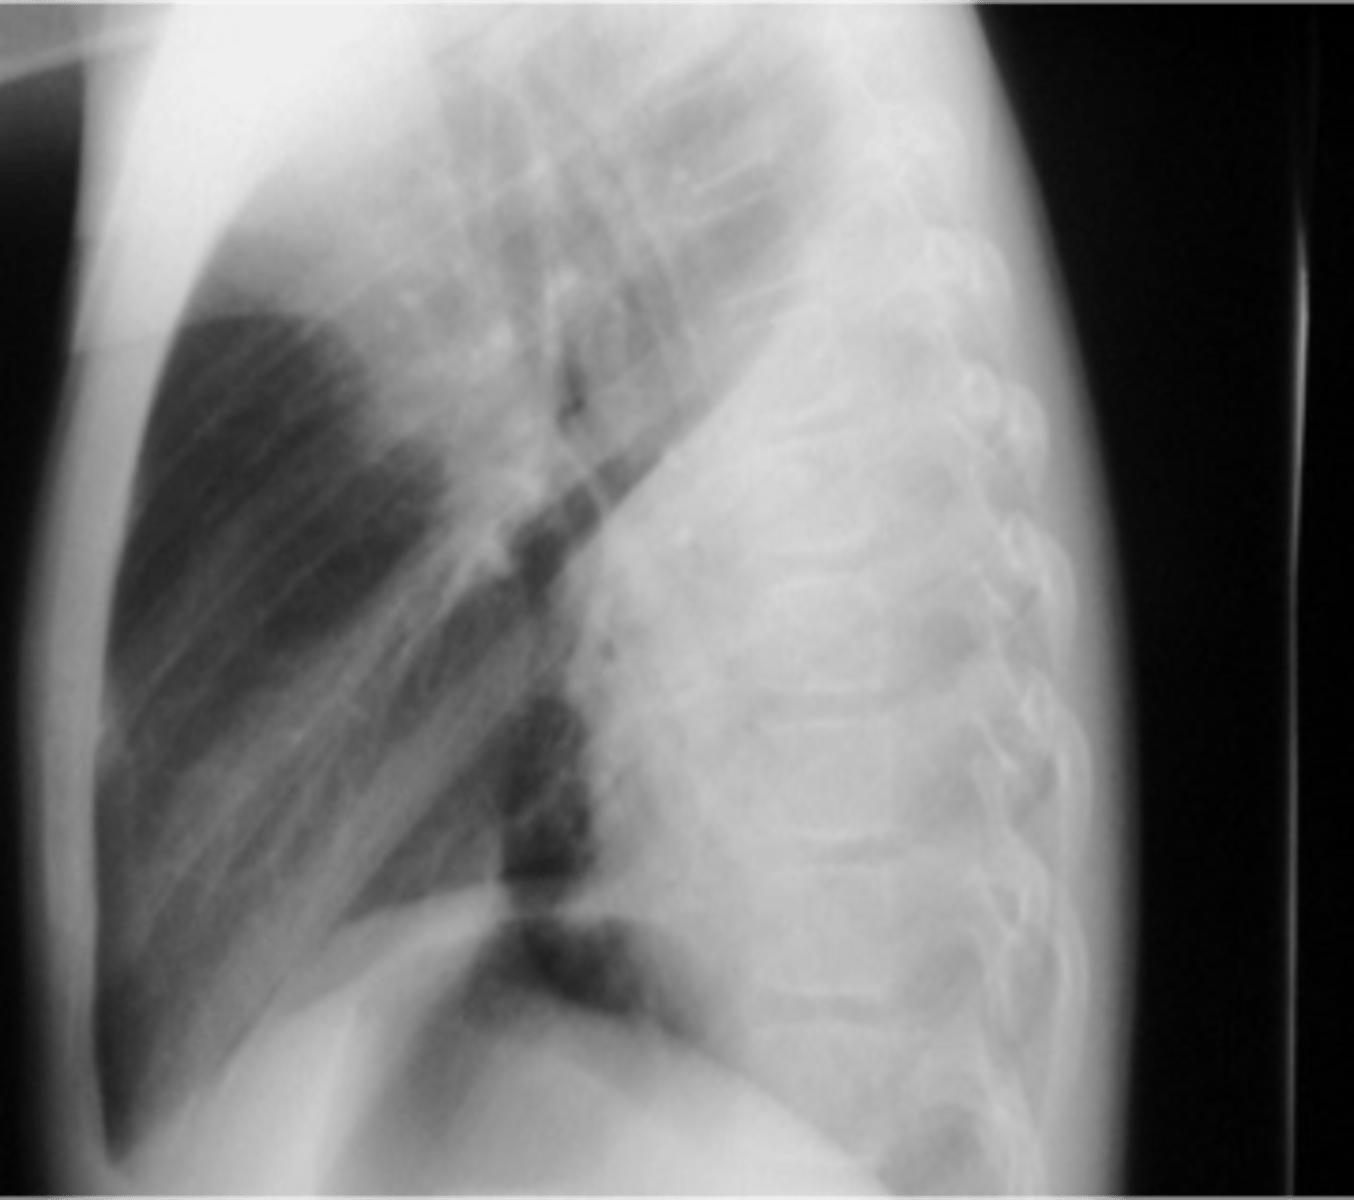

vertebral bodies are lighter (white) than normal on lateral x-ray view

spine sign